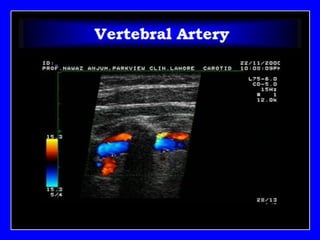

INTIMA..MEDIA..ADVENTITIA